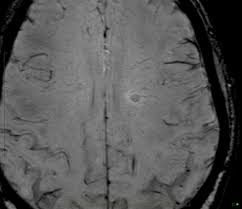

Widespread use of mri (magnetic resonance imaging) has revolutionized the ability to diagnose multiple sclerosis. Optic nerve evaluation within normal limits. Magnetic resonance imaging (mri) plays a crucial role in multiple sclerosis (ms) diagnosis, disease monitoring, prognostication, and research. There are multiple lesions in the spinal cord. Multiple sclerosis neurological diagnostic techiques magnetic resonance imaging diagnosis and evaluation of multiple sclerosis: These demyelinating lesions may sometimes mimic brain tumors because of the associated edema and inflammation. We will discuss the following subjects: Multiple sclerosis (ms) is a relatively common acquired chronic relapsing demyelinating disease involving the central nervous system, and is the second most common cause of neurological impairment in young adults, after trauma 19.characteristically, and by definition, multiple sclerosis is disseminated not only in space (i.e. Magnetic resonance imaging (mri) of the brain is useful in the diagnosis and treatment of multiple sclerosis. An mri scan is abnormal in more than 95% of people recently diagnosed with ms. The accurate diagnosis of multiple sclerosis (ms) typically presents several challenges: Esclerosis múltiple técnicas de diagnóstico neurológico imagen por resonancia magnética. Lo que el radiólogo debe conocer e informar.

Balo Concentric Sclerosis Radiology Reference Article Radiopaedia Org from prod-images-static.radiopaedia.org An mri scan is abnormal in more than 95% of people recently diagnosed with ms. Abnormalities show up on scans from many illnesses other than ms. Conventional magnetic resonance imaging (mri) has routinely been used to improve the accuracy of multiple sclerosis (ms) diagnosis and prognosis. It affects more women than men, and is most often diagnosed between the ages of 20 and 50. Usually, mri is the only imaging modality needed for imaging patients with ms, and it far surpasses all other tests. Its high sensitivity for the evaluation of inflammatory and neurodegenerative processes in the brain and spinal cord has made it the most commonly used technique for the evaluation of patients with ms. To describe the factors that are associated with gadolinium enhancement on mri in patients with multiple sclerosis (ms) and symptoms of relapse. There are multiple lesions in the spinal cord.

Multiple Sclerosis The Role Of Mr Imaging American Journal Of Neuroradiology from www.ajnr.org These demyelinating lesions may sometimes mimic brain tumors because of the associated edema and inflammation. Amsterdam university medical center and university college london and alrijne hospital leiderdorp, the netherlands. But abnormal mri results do not always mean that you have ms. Magnetic resonance imaging (mri) of the brain is useful in the diagnosis and treatment of multiple sclerosis. Mri has made it possible to visualize and understand much more about the underlying pathology of the disease. It is the preferred imaging method to help establish a diagnosis of ms and to monitor the course of the disease. This article is an updated version of the 2013 article and focusses on the role of mri in the diagnosis of multiple sclerosis. We will discuss the following subjects: